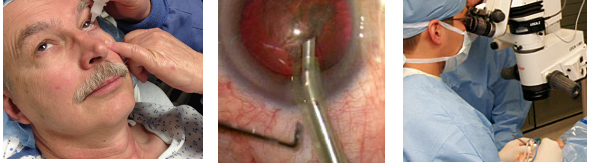

L’intervento

È effettuato in sala operatoria; ha una durata per lo più tra i 10 ed i 20 minuti, salvo casi complessi. La durata dell’intervento non è connessa al risultato clinico e visivo. L’intervento è ambulatoriale, con ritorno a casa dopo circa un’ora.

In anestesia topica l’esecuzione dell’intervento è controindicata solo quando la collaborazione appare molto scarsa o l’intervento impegnativo, Allora s’impiega l’anestesia locale, oppure l’anestesia generale. La scelta è effettuata su parere dell’oculista e condivisa con il paziente. La cataratta è rimossa mediante facoemulsificazione tramite un’incisione inferiore ai 2,5 millimetri tra il bianco (sclera) e la cornea. In casi rari sono consigliate tecniche diverse.

Il cristallino artificiale, in materiali speciali areattivi, è inserito sull’involucro trasparente della cataratta (capsula). L’incisione non ha bisogno di sutura, che è usata in qualche caso per sicurezza e rimossa in ambulatorio dopo qualche settimana. Al termine dell’intervento si applica una lente a contatto protettiva per 24 ore.